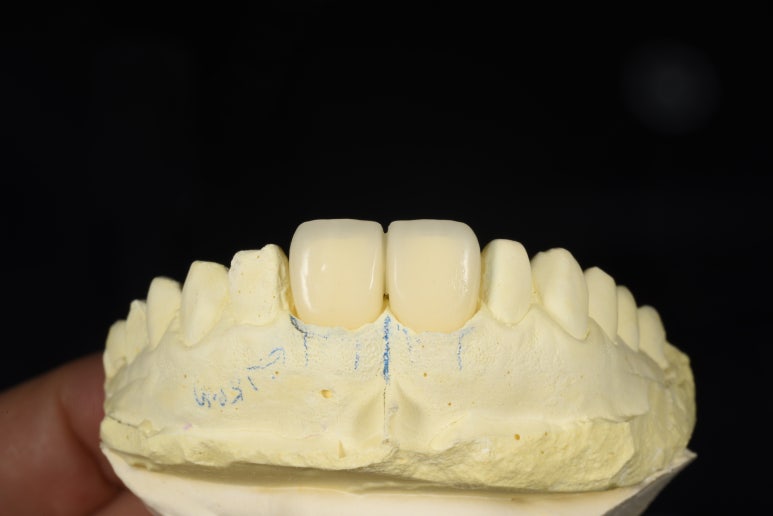

크라운 제작과정

완성된 크라운